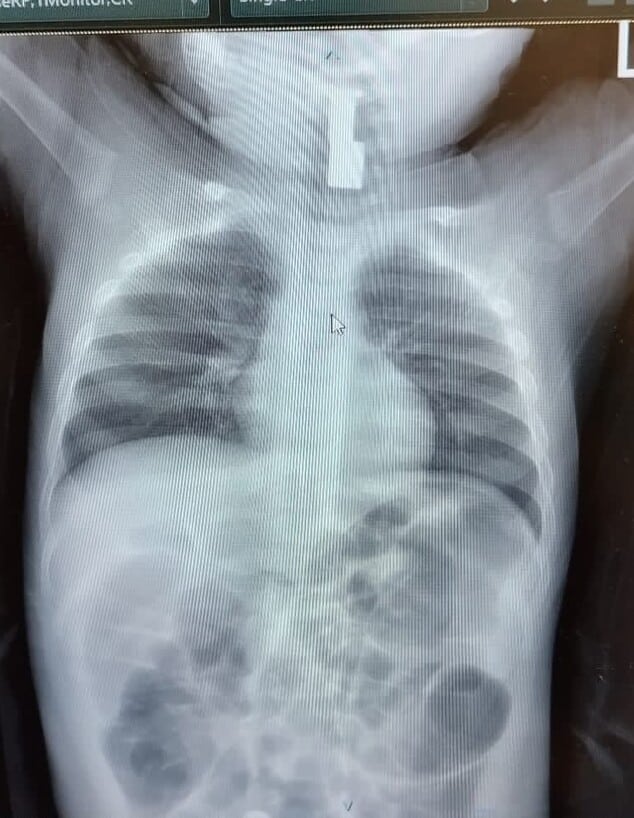

צילום של החפץ | צילום: הדסה

מעט לפני חצות, ההורים המודאגים הגיעו למיון ילדים בהדסה עין כרם. שם עבר זאב בדיקות מקיפות על ידי צוות המחלקה, אך לא נמצא בהן משהו חריג. בשלב זה, ניגשה אליהם רופאת הילדים ד"ר רבקה גלעד, והציעה לבצע לזאב צילום חזה, כדי להשלים את מכלול הבדיקות הרפואיות ולהרגיע את ההורים המודאגים. "כשקיבלתי את תוצאות הצילום הייתי מופתעת בעצמי", מספרת הד"ר. "התינוק היה כל כך חיוני, וממש לא ציפיתי לראות גוף זר, וודאי שלא כזה גדול". לדבריה, ההחלטה להפנות אותו לצילום נקבעה על סמך רצונה למצות את כלל הבדיקות הנגישות. "המחשבה על מה שהיה יכול לקרות אם לא היינו עושים צילום, מטלטלת אותי בכל פעם שאני חושבת על המקרה", היא אומרת.

לאחר הממצא המפתיע, התקשרה מייד הרופאה לד"ר אחמד סיאג', רופא אא"ג, שחבר אליה לטיפול בתינוק. הוא זיהה בצילום גוף זר במרקם מתכתי, והחדיר לזאב מצלמה זעירה דרך האף לכיוון הגרון. שם, הוא הבחין במשהו בוהק שמסתיר את מיתרי הקול. "לא יכולתי לראות את דרכי הנשימה של התינוק, והבנתי שהוא במצב מסכן חיים", הוא מספר. ד"ר סיאג' התקשר לצוות חדרי הניתוח והורה להם להכין את החדר באופן מיידי. "הבהלנו את התינוק אל חדר הניתוח, שם המרדימים הרדימו אותו באמצעות מסיכת חמצן. בהליך רגיש ועדין הורמה הלשון של זאב ושלפתי בזהירות יתירה את הגוף הזר, על מנת שחלילה לא אגרום לדחיפתו פנימה יותר".